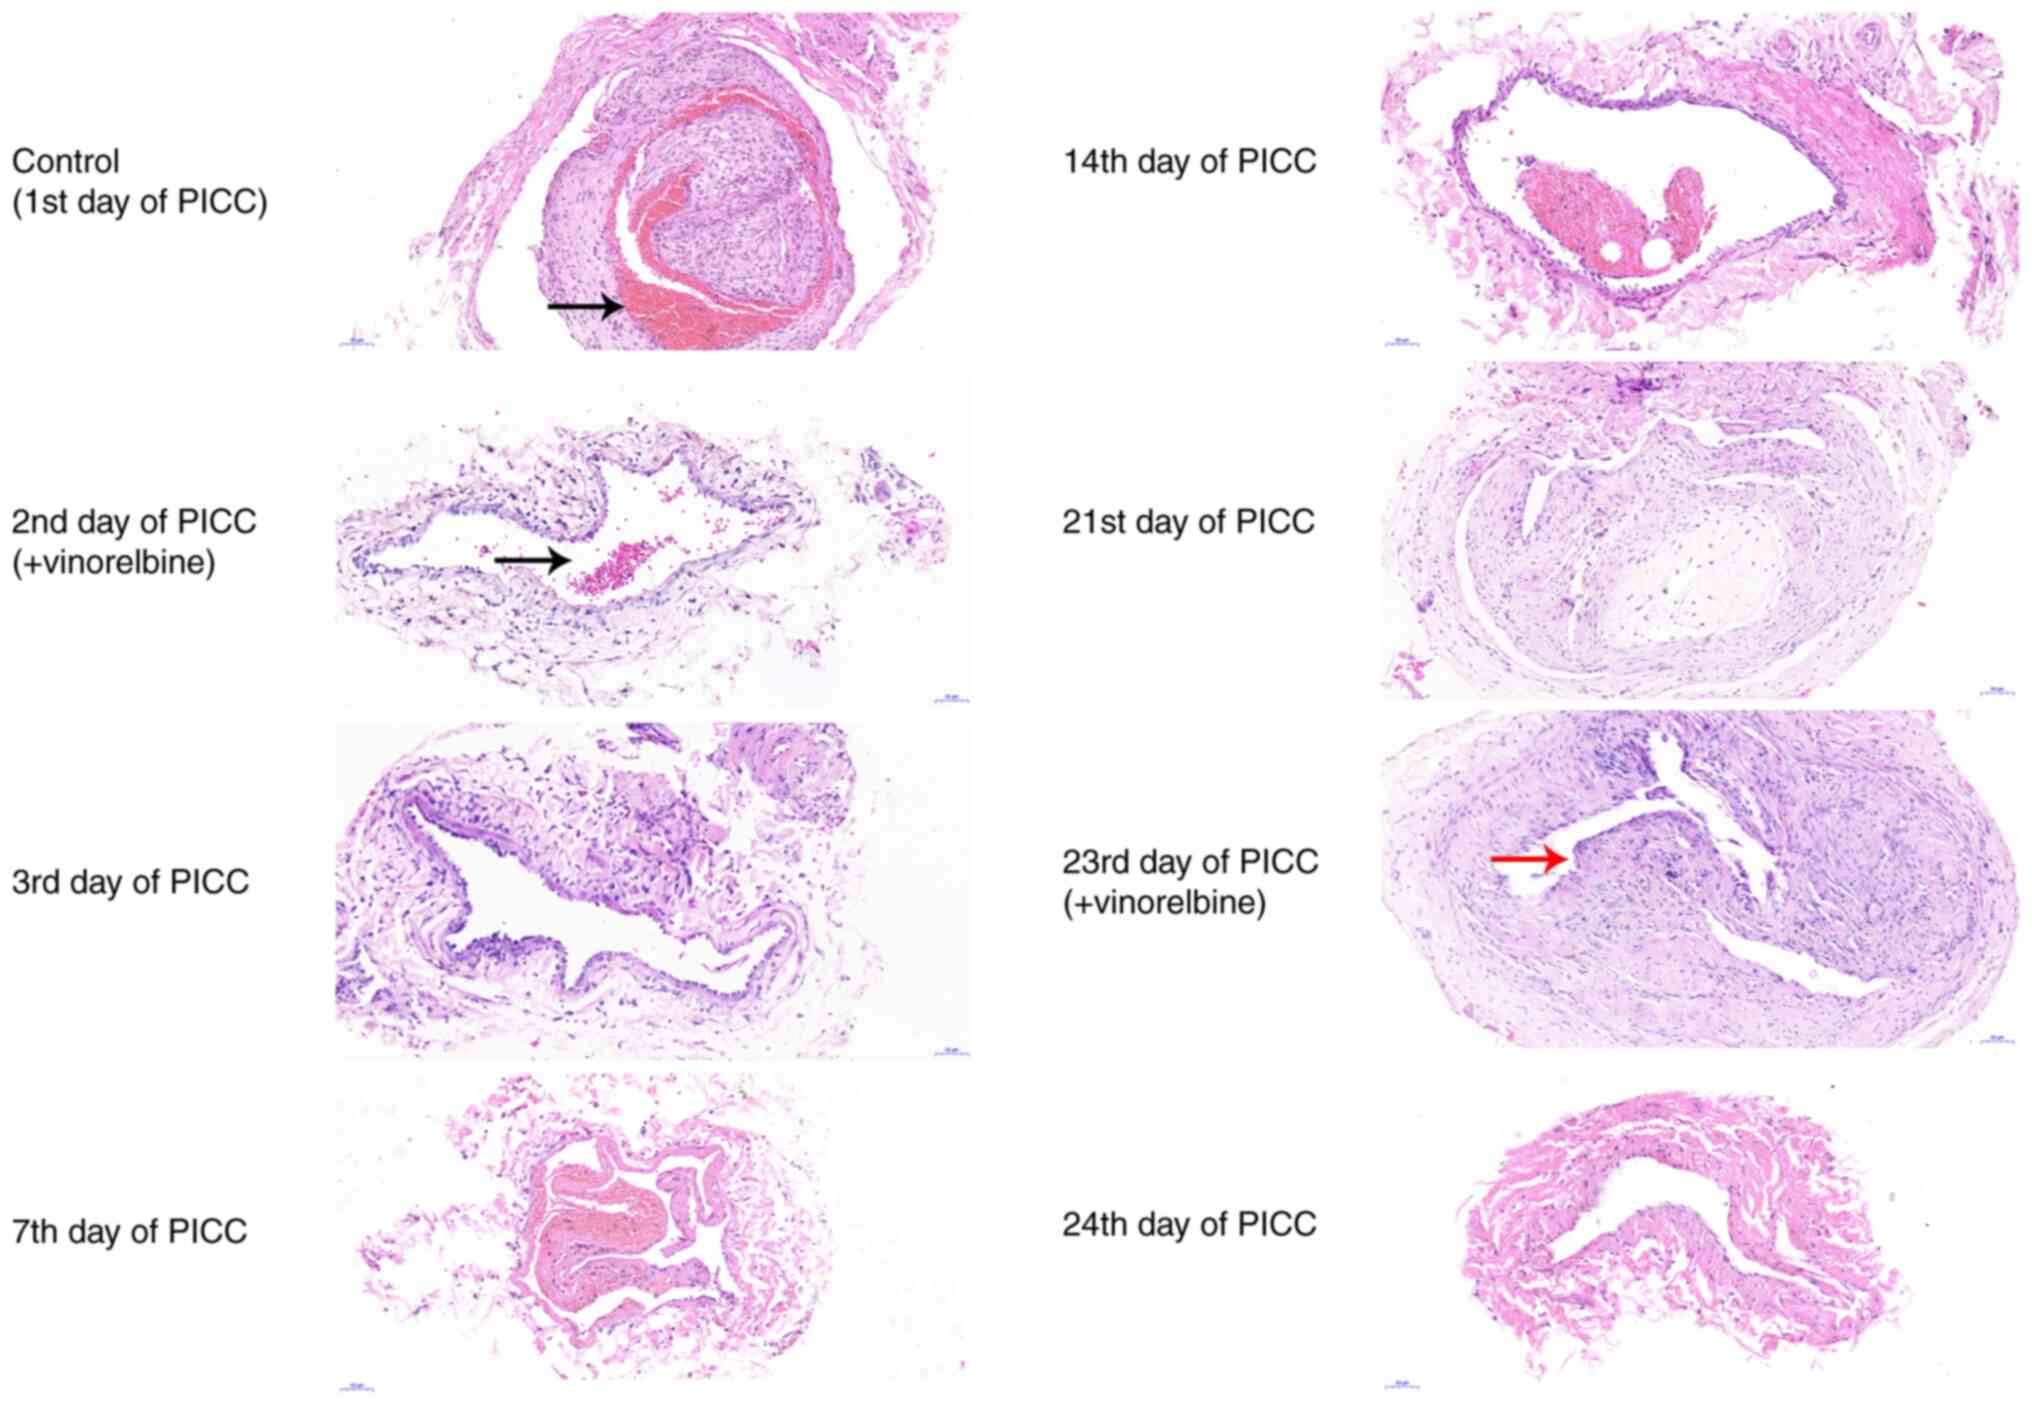

At different time periods, the PICC tube was removed and the two segments at the front and back of the catheter were surgically dissected. H&E staining of the middle of the catheter was performed to observe catheter-related thrombosis. On the 1st day of PICC implantation, the H&E staining results revealed that a thrombus filled the catheter (Fig. 4). On the 2nd day of PICC implantation, no thrombus was observed in the catheter after administration of vinorelbine. The catheter-related thrombus was continuously monitored on the 3rd, 7th, 14th and 21st days of PICC implantation. As indicated by the H&E staining results, there was no thrombus in the catheter. On the 23rd day of PICC implantation, a small thrombus was observed in the catheter. However, the thrombus was no longer visible on the 24th day. Collectively, the results indicated that catheter-related thrombosis primarily occurred on the 1st day of PICC implantation and the 23rd day of chemotherapy administration.

Figure 4

Dynamic monitoring of catheter-related thrombosis in rabbits with PICC administration of vinorelbine. Hematoxylin and eosin staining was performed to assess catheter-related thrombosis in rabbits with PICC placement at eight different time points. Arrows indicate the thrombus. Magnification, x15. Scale bar, 100 µm. PICC, peripherally inserted central catheter.

Dynamic monitoring of ear vein thrombosis after administration of vinorelbine via PICC

H&E staining was performed to examine the pathological changes in ear vein tissues at numerous time points (Fig. 5). On the 1st day of PICC implantation, the intima of the ear veins was irregularly ruptured, and the lumen was characterized by thrombosis. On the 2nd day of catheterization, there was slight ear vein thrombosis, the intima was irregularly ruptured, and inflammatory cell infiltration was observed following vinorelbine administration. On the 3rd, 7th and 14th days of PICC implantation, ear vein thrombosis and inflammatory cell infiltration were notably improved, the intima was hyperplastic, and scars were formed in the lumen of the ear veins. Furthermore, the media and adventitia had no obvious lesions, and the lumen was not completely occluded. On the 21st and 23rd (after vinorelbine administration) days of PICC implantation, the results revealed that there were evident scars and inflammatory cell infiltration in the lumen. On the 24th day, the blood vessels of the ear veins were not damaged, there was no obvious scar in the lumen and thrombosis had disappeared. Therefore, the results indicated that ear vein thrombosis was primarily caused by PICC puncture, and administration of vinorelbine may induce inflammatory cell infiltration.

Figure 5

Dynamic monitoring of ear vein thrombosis in rabbits with PICC administration of vinorelbine. Hematoxylin and eosin staining was performed to assess the ear vein thrombosis in rabbits with PICC placement at eight different time points. Black arrows indicate ear vein thrombosis. Red arrow indicates inflammatory cell infiltration. Magnification, x20. Scale bar, 50 µm. PICC, peripherally inserted central catheter.

Dynamic monitoring of pathological injury in the anterior vena cava after administration of vinorelbine via PICC

The end of the anterior vena cava was obtained at different time periods to investigate pathological injury via H&E staining. On the 1st day of PICC implantation, the vascular intima of the anterior vena cava was irregularly ruptured (Fig. 6). Furthermore, the vessel wall was thickened, which was accompanied by immune cell infiltration. On the 2nd (after vinorelbine administration), 3rd and 7th days of PICC implantation, the vascular intima of the anterior vena cava was relatively intact, with a slightly thickened wall. Moreover, inflammatory cell infiltration was distinctly ameliorated. On the 14th and 21st days, the vascular intima of the anterior vena cava was intact and the wall was normal. However, low level immune cell infiltration was observed. On the 23rd day of PICC implantation after administration of vinorelbine, there was distinct inflammatory cell infiltration in the anterior vena cava. On the 24th day, the vascular intima of the anterior vena cava was relatively intact, the wall was normal and there was almost no infiltration of inflammatory cells. These results indicated that vinorelbine administered via PICC could induce phlebitis, and over time phlebitis was gradually ameliorated within the first cycle of vinorelbine and phlebitis was significantly alleviated within 1 day of the second cycle of vinorelbine

Figure 6

Dynamic monitoring of pathological injury in the anterior vena cava in rabbits with PICC administration of vinorelbine. Hematoxylin and eosin staining was performed to assess the pathological changes in the anterior vena cava tissues in rabbits with PICC placement at eight different time points. Black arrow indicates irregularly ruptured vascular intima. Red arrows indicate immune cell infiltration. Magnification, x20. Scale bar, 50 µm. PICC, peripherally inserted central catheter.